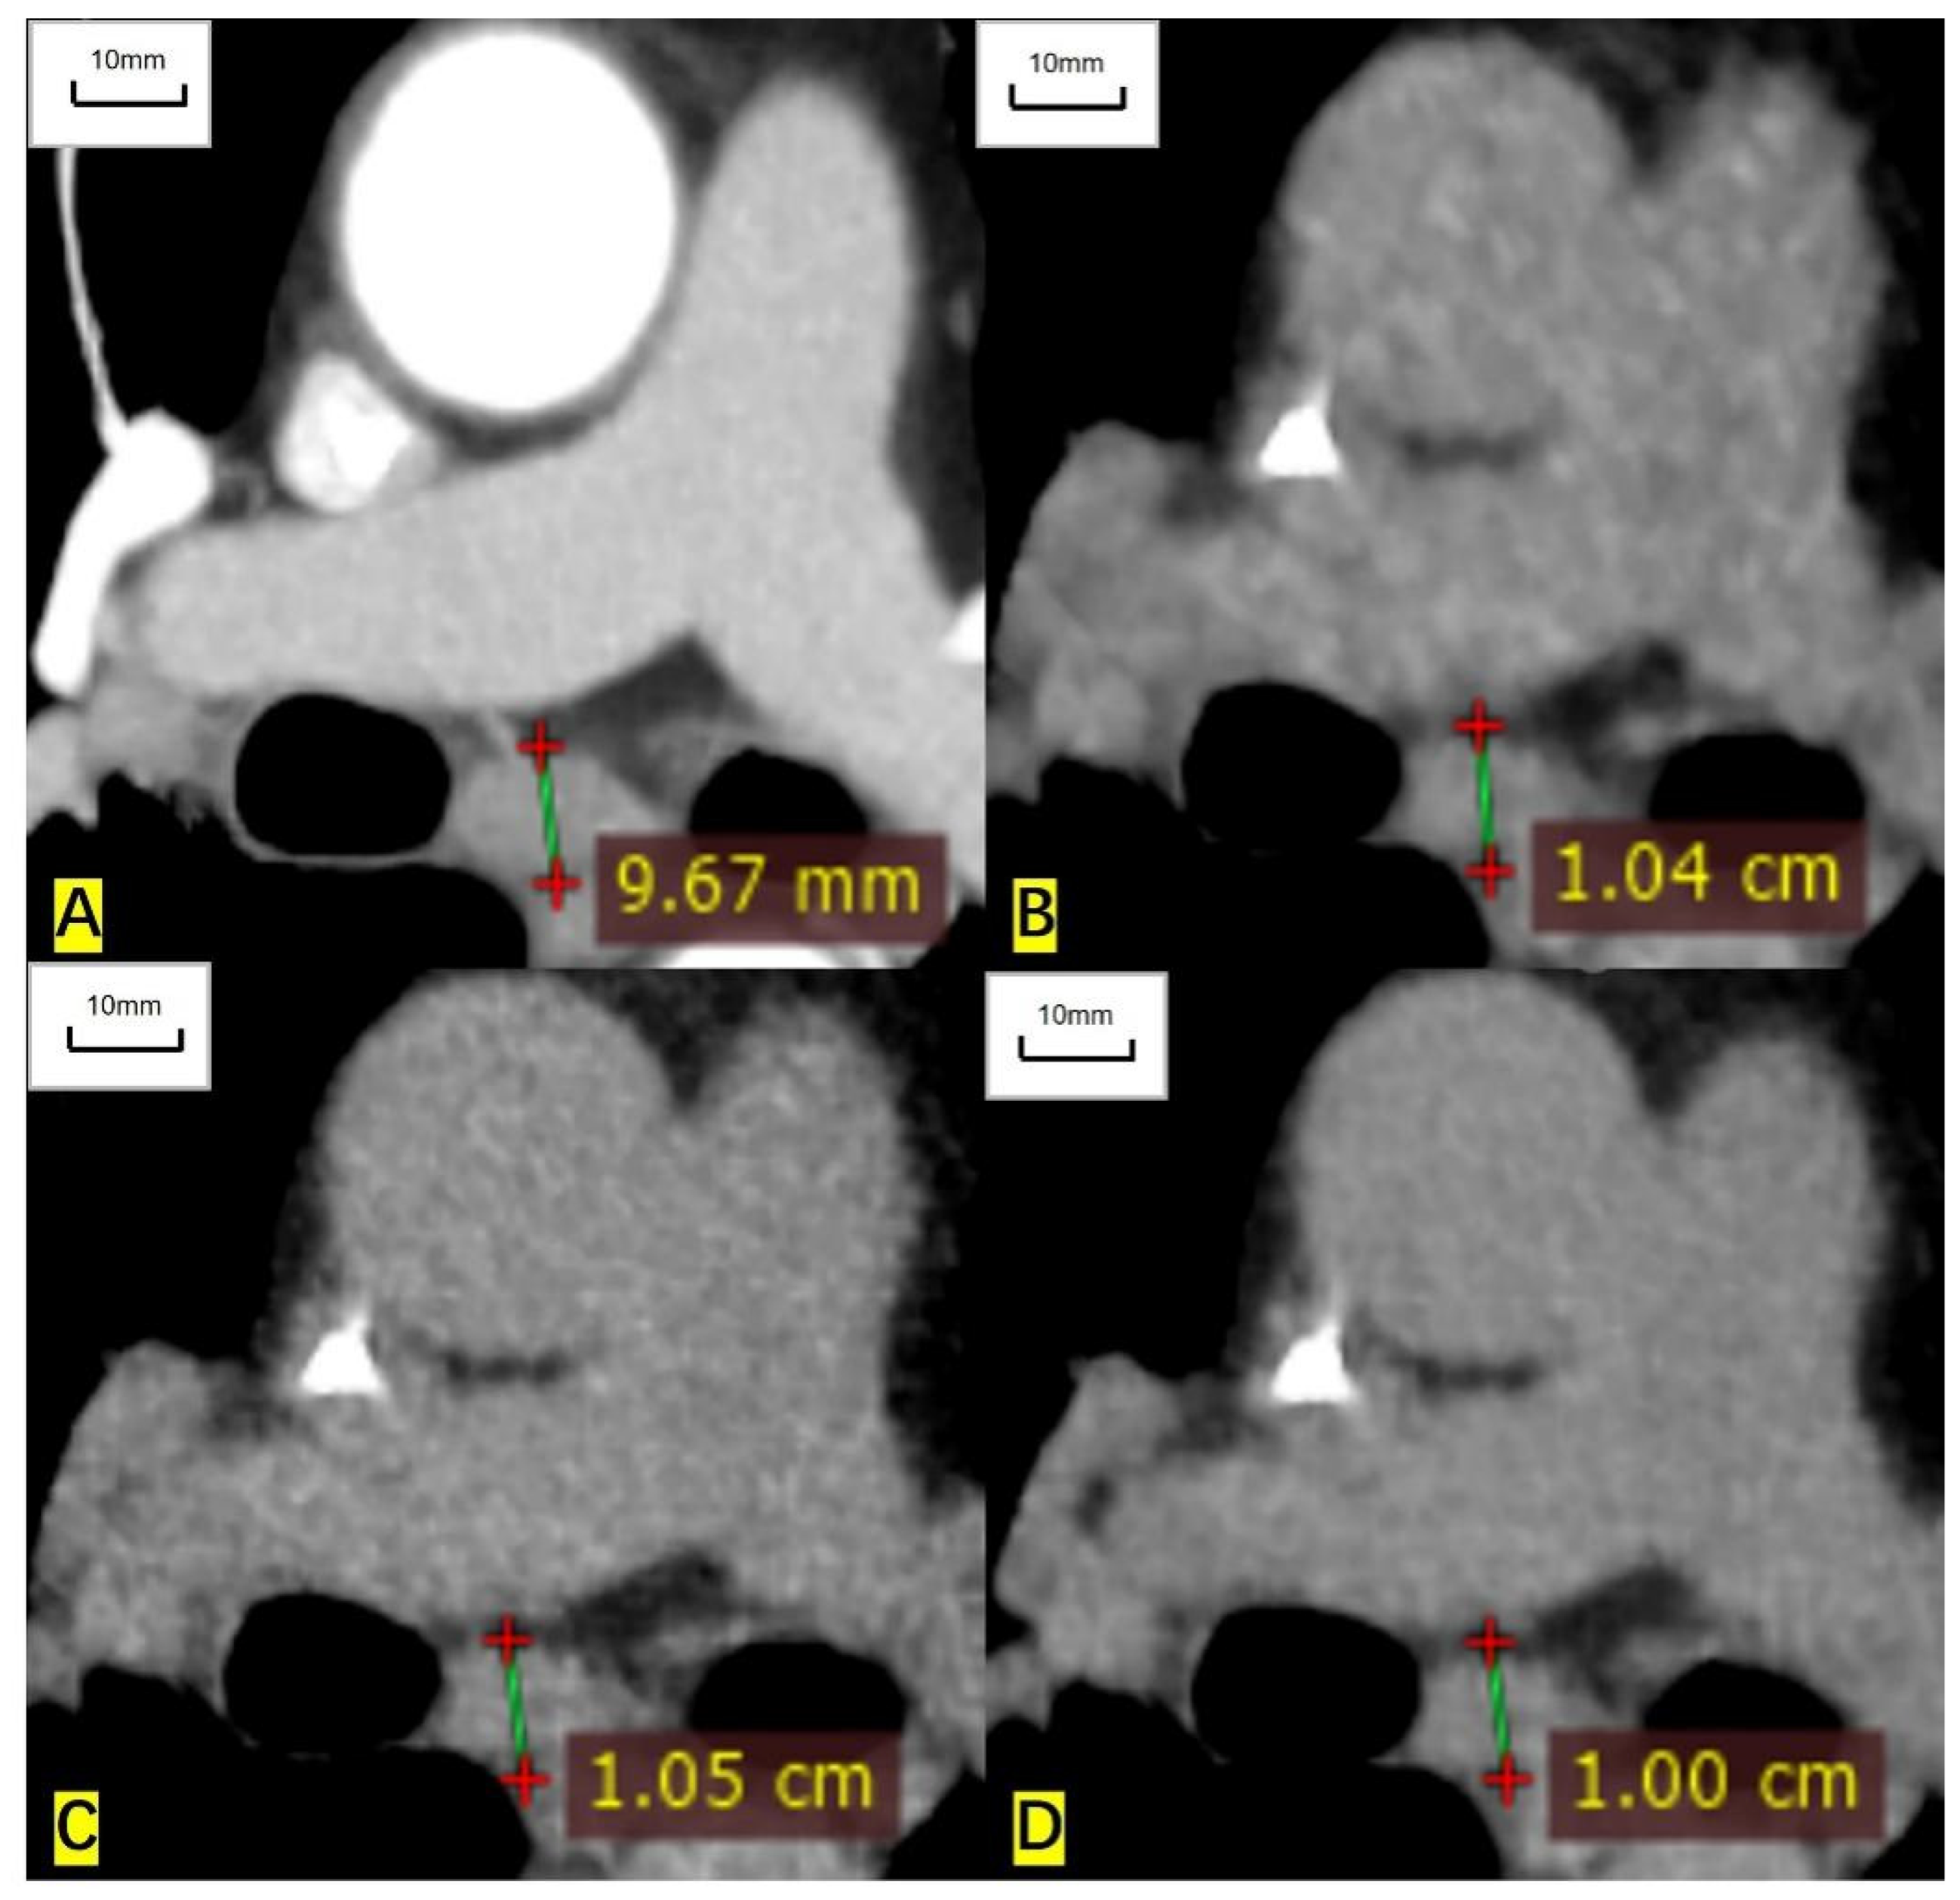

Figure 2.

A 75-year-old woman had a lymph node in the left hilum and the histological result was adenocarcinoma. (A) The short diameter measured on the contrast-enhanced CT image is 32.1 mm. (B) The measured short diameter on the ASIR-V-80% reconstructed image is 33.3 mm. (C) The measured short diameter on the DLIR-M image is 33.4 mm. (D) The measured short diameter on the DLIR-H images is 32.7 mm. The short diameter is overestimated by 3.7%, 4.0%, and 1.9%, respectively, compared with that of contrast-enhanced CT.

For RECIST-defined pulmonary target lesions, the correlation coefficient of measured diameter between ULDCT and contrast-enhanced CT was 0.999 (95% CI: 0.998 to 0.999), 0.998 (0.997 to 0.999), and 0.999 (0.999 to 1.000) for ASIR-V-80%, DLIR-M, and DLIR-H images, respectively. For mediastinal lymph nodes, the correlation coefficient was 0.997 (0.995 to 0.999), 0.997 (0.995 to 0.998), and 0.999 (0.998 to 1.000), respectively. For hilar lymph nodes, the correlation coefficient was 0.993 (0.979 to 0.997), 0.995 (0.984 to 0.998), and 0.997 (0.991 to 0.998), respectively. The measured diameters of target lesions in ULDCT were highly correlated with those in contrast-enhanced CT (Table 2, Figure 1 and Figure 2).